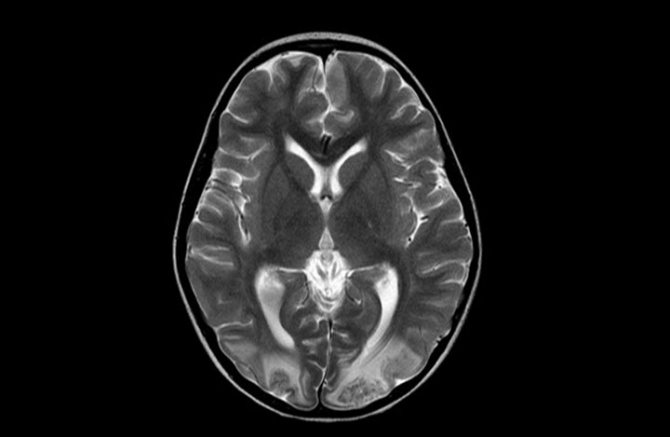

МРТ при асимметрии боковых желудочков

У здорового человека обеспечивается постоянная взаимосвязь между описанными структурами. Блокада одной из желудочков приводит к увеличению количества ликвора с последующим повышением давления. МРТ обнаруживает асимметрию желудочков в ранней стадии до возникновения клинических симптомов. Без признаков сложно определить показания к направлению на магнитно-резонансную терапию. На МРТ головного мозга четко прослеживается ассиметрия желудочков.

Выявить признаки незначительной дилатации боковых желудочков удается с помощью такого современного метода диагностического обследования, как магнитно-резонансная томография. На получаемых изображениях мозговых структур можно детально увидеть область расширения,площадь поражения, вовлеченность в процесс соседних тканей мозга.